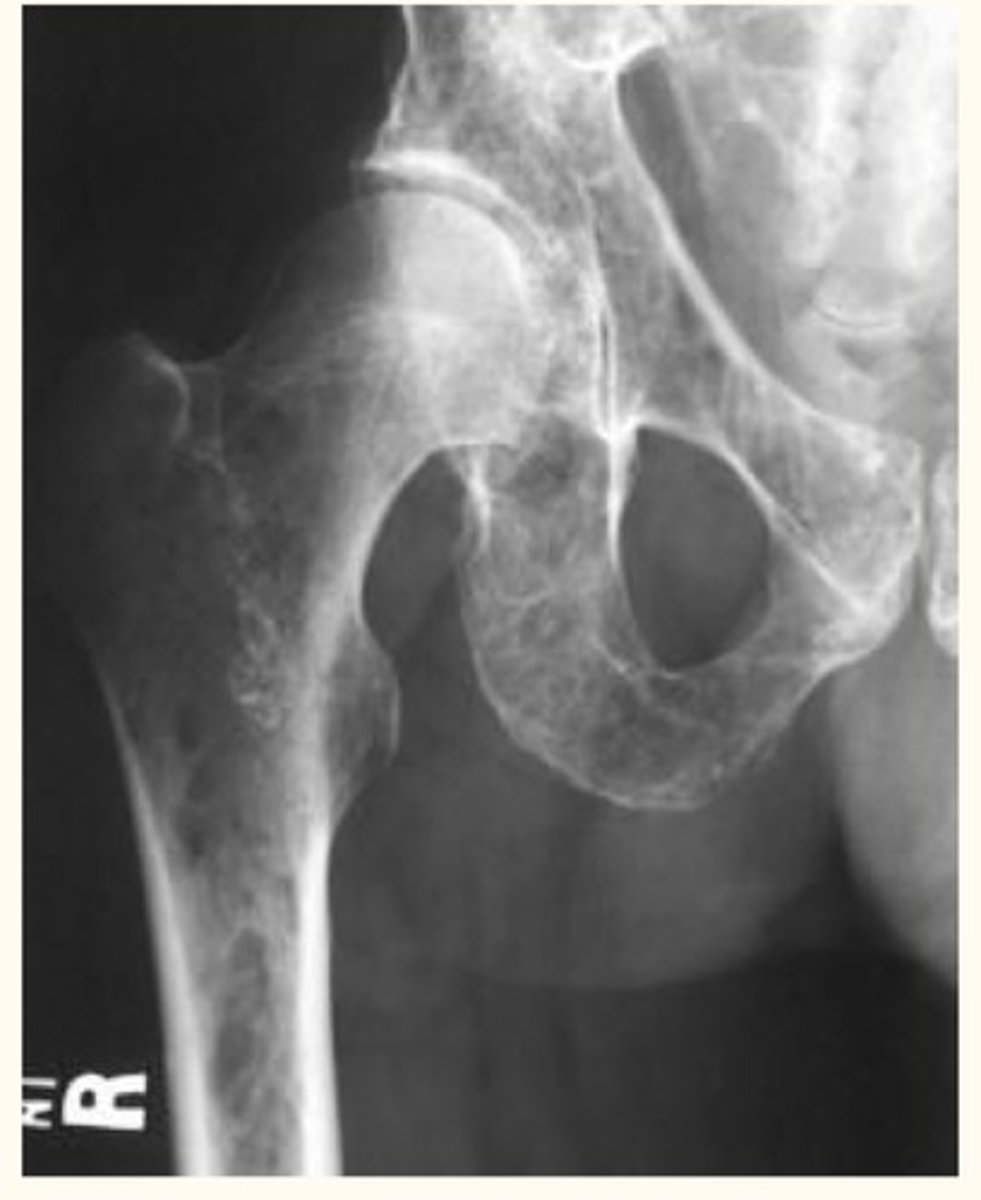

Multiple Myeloma

Definition: Malignancy of plasma cells

Pathogenesis: Terminally differentiated plasma (B) cells secrete a TON of antibodies

Etiology: N/A

S+S: Bone pain, fractures, loss of appetite, weight loss, fatigue, kidney failure

Treatment: Chemo + palliative care :(

<p>Definition: Malignancy of plasma cells</p><p>Pathogenesis: Terminally differentiated plasma (B) cells secrete a TON of antibodies</p><p>Etiology: N/A</p><p>S+S: Bone pain, fractures, loss of appetite, weight loss, fatigue, kidney failure</p><p>Treatment: Chemo + palliative care :(</p>

Defining characteristics of Multiple Myeloma

High antibody level, osteolytic lesions in bones

<p>High antibody level, osteolytic lesions in bones</p>